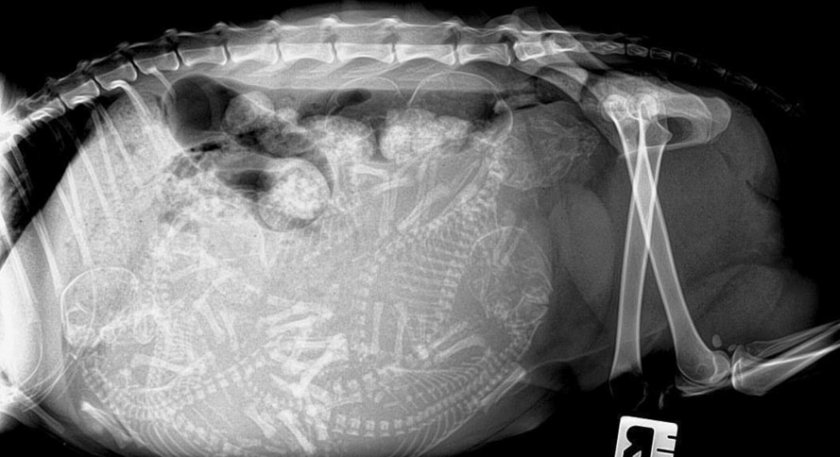

Рентген

После 40 дня беременности сколько плодов у кошки покажет рентген. Более раннее проведение обследования не информативно, потому что у зародышей еще не образовалась костная ткань.

В основном рентген делают именно для того, чтобы узнать точное количество плодов. А также исключить ложную беременность и пиометру.

Ваша домашняя любимица начнет прибавлять в весе на 4-5-ю неделю, вес увеличится на один-два килограмма в зависимости от количества котят. На рентгеновском снимке можно увидеть скелетную структуру котят на 44-й день, но не делайте рентген без крайней необходимости.